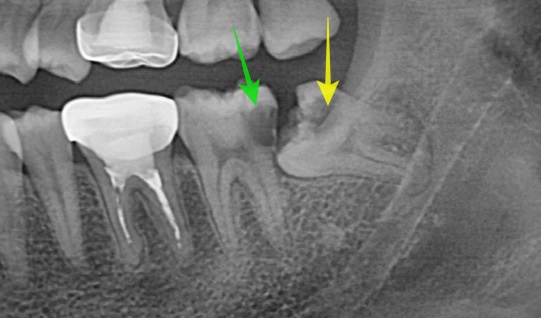

3) 사랑니 및 인접 치아 충치

→ 닿기 힘든 부위에 음식물이 끼어 충치 발생, 심하면 앞어금니까지 손상

사진 1,2번과 같은 상태가 오랫동안 유지되면 사랑니(노란 화살표) 뿐 아니라 그 앞의 치아까지도(초록 화살표) 충치가 생깁니다.